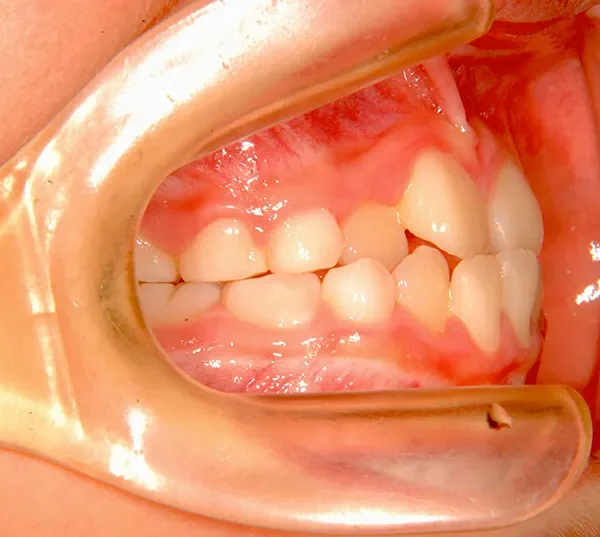

【子供の矯正(一期)】叢生・切端咬合・受け口・永久歯が生える隙間がない・非抜歯症例・8歳男子【K.Y様】

まずは装置で歯のアーチを広げ、歯の生えるスペースを作り、中に入ってる上の前歯を外に押し出して正常な噛み合わせにします。

治療回数44回、5年5ヶ月の治療期間で矯正治療を終了しました。

主訴が改善され、ご満足頂きました。

治療終了後